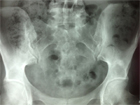

Devant cette image condensante iliaque qui avait grossi en 8 ans, une scintigraphie osseuse a été faite (Figure 3) qui a montré une hyperfixation unique.

Au scanner (Figure 4), la condensation était homogène bien limitée, ce qui a permis de confirmer le diagnostic d'îlot condensant bénin qui aurait pu être fait même sans les examens d'imagerie pour les radiologues de Lariboisière, car il est des exemples d'îlot condensant bénin qui